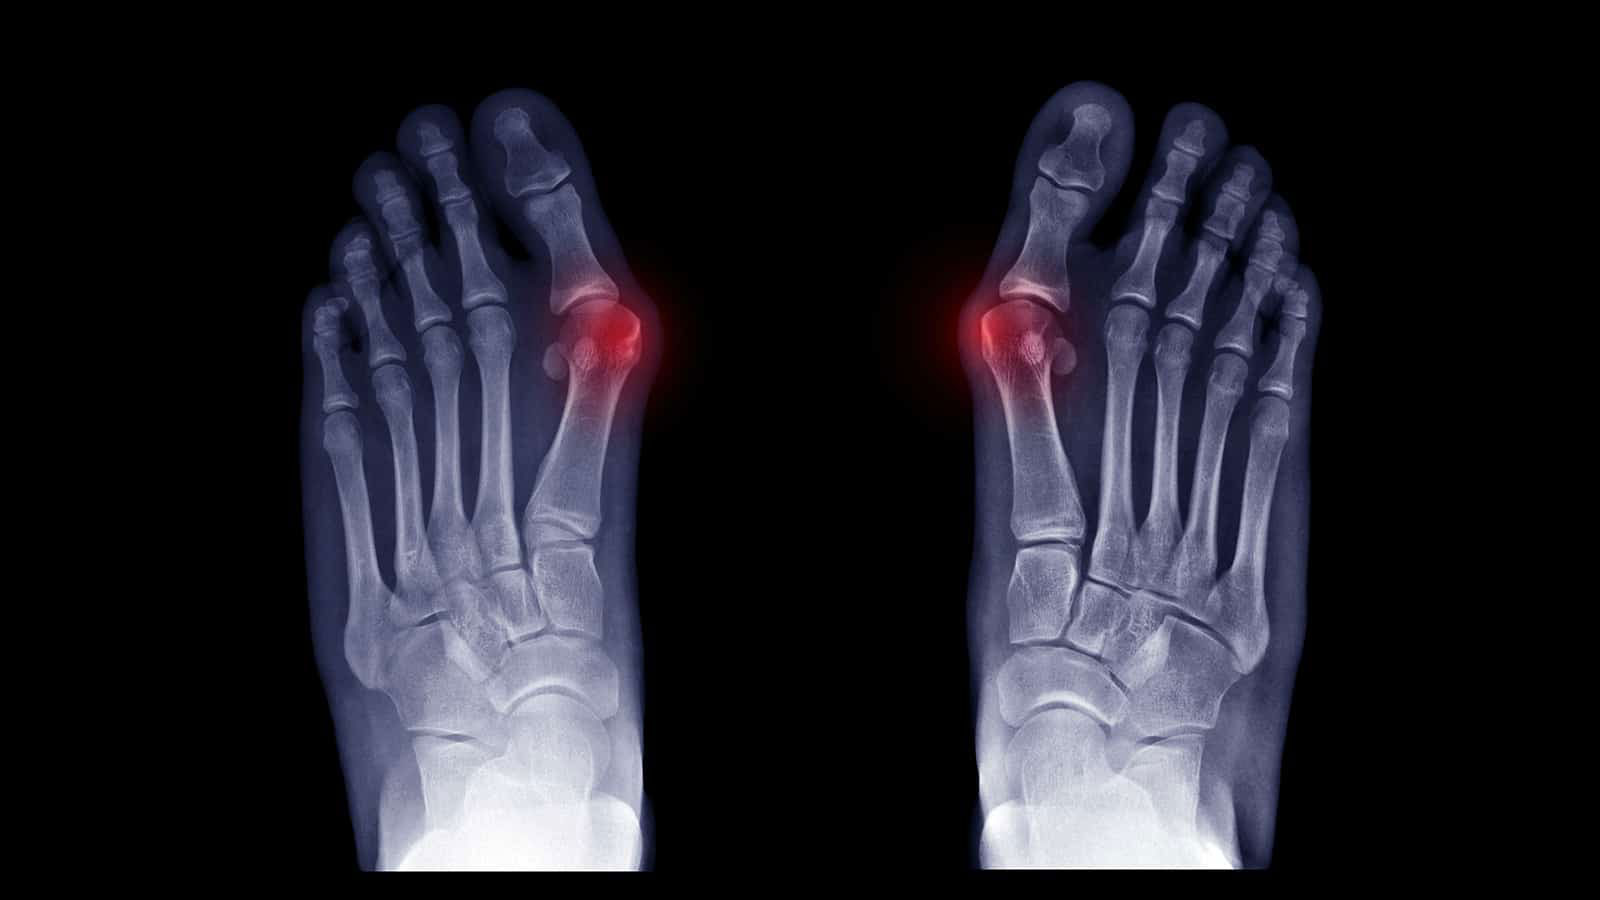

A bunion is not a growth of new bone. It is a dislocation of the joint. When the first metatarsal (the long bone in your foot) shifts outward, it forces the big toe to angle inward toward your smaller toes. This misalignment causes the joint to “sublux,” or move out of its socket, which creates the characteristic bump.

Regular checks and x-rays

Biomechanical Assessment & X-Ray Review

We use [Video Gait Analysis] to see how your bunion is affecting your walk. If necessary, we refer you for weight-bearing X-rays to measure the exact “intermetatarsal angle” and determine the stage of the deformity.